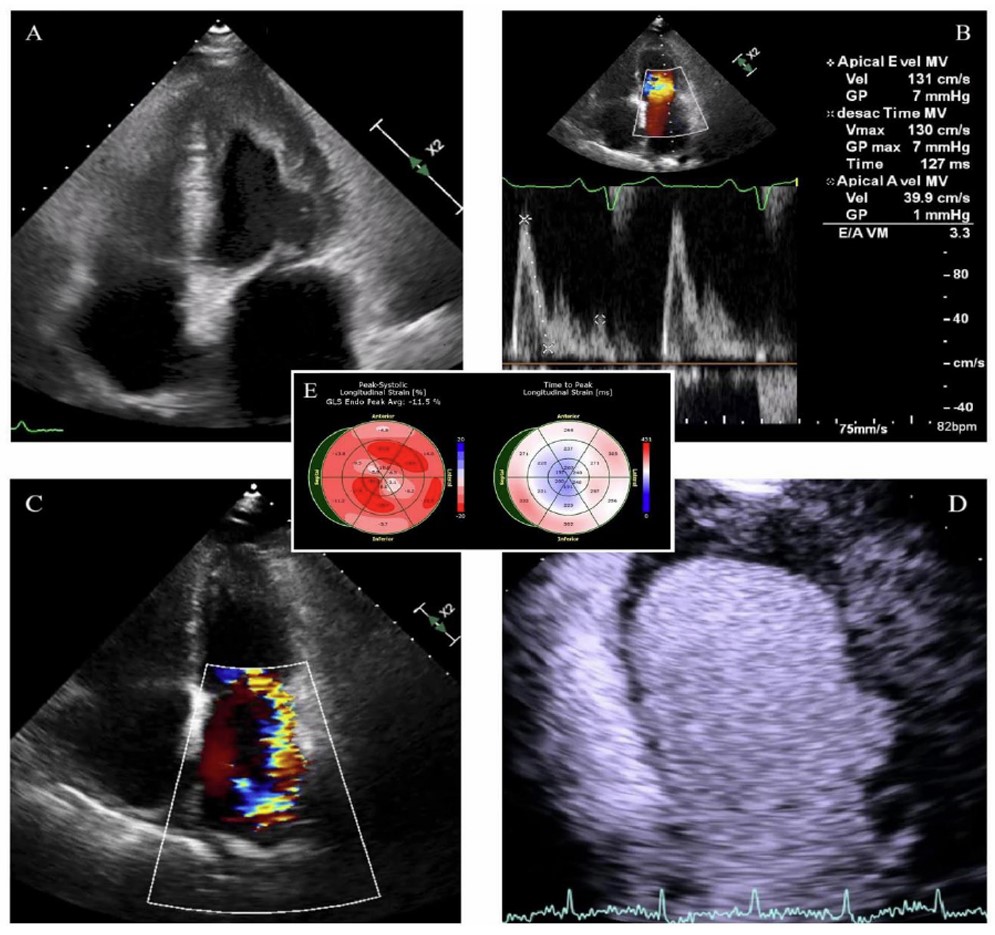

The Transthoracic Echocardiogram (TTE), which was normal prior to chemotherapy, now showed reduced LV volumes, severe diastolic restriction, and apical obliteration due to an intraventricular thrombus. Systolic function remained intact, with no obvious regional wall motion issues. However, global longitudinal strain was significantly reduced (at -11%), predominantly impacting the apical segments (Fig. 2). The Right Ventricle (RV) appeared dilated with decreased systolic function. Significant Mitral Regurgitation (MR) and very severe pulmonary hypertension were suspected (estimated systolic pulmonary artery pressure, 105 mmHg) (Supp. videos 1-3). Depletive therapy and oral anticoagulation were initiated.

Transthoracic echocardiography, apical four-chamber view, showing: (A) a left ventricle with reduced volumes secondary to extensive apical obliteration by an intraventricular thrombus; (B) a transmitral filling pattern consistent with grade III diastolic dysfunction; (C) significant mitral regurgitation with right ventricular dilation and biatrial enlargement; (D) an obliterative apical thrombus with low enhancement following ultrasound contrast administration, associated with a basal inferolateral aneurysm; (E) significantly compromised GLS (at -11%), predominantly affecting the apical segments, with a relatively increased time-to-peak at the basal level, supporting the hypothesis of apical endomyocardial dysfunction or structural impairment, as well as impaired conduction involving the basal segments.